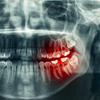

Bruxismo

Es cuando una persona rechina los dientes (deslizar o frotar los dientes de atrás hacia adelante uno sobre el otro).

Rechinar los dientes puede ejercer presión sobre los músculos, tejidos y otras estructuras alrededor de la mandíbula. Los síntomas pueden causar problemas de la articulación temporomandibular (ATM).

El rechinamiento puede desgastar los dientes y puede ser tan ruidoso en las noches como para molestar el sueño de los compañeros de dormitorio.

• Aumento de los problemas dentales o de la ATM

• Dientes fracturados

• Encías retraídas